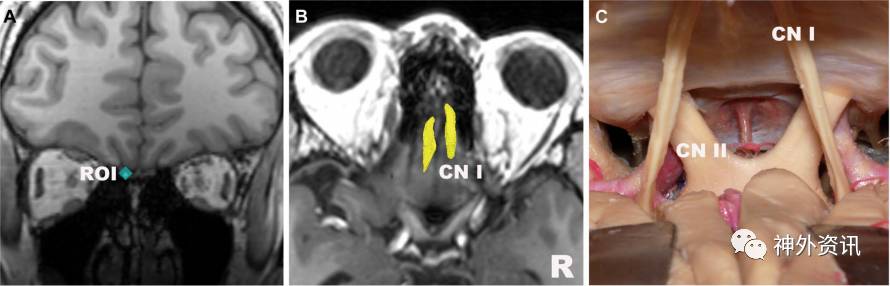

图2. 嗅神经。A.ROI置于冠状位嗅神经束上;B.嗅神经束高分辨率纤维束成像;C.对应解剖图(B图上面观)。CN:颅神经。